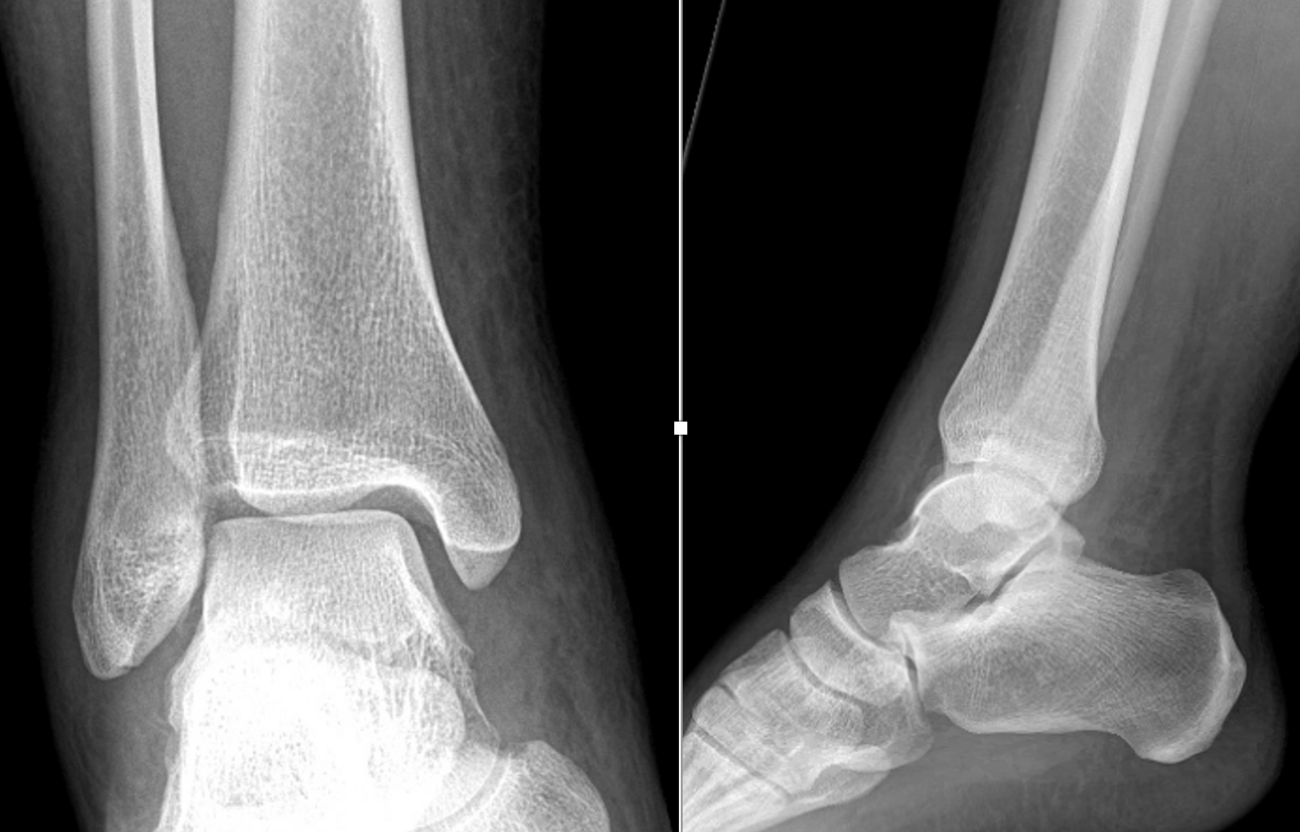

Her initial injury radiographs revealed a small lucent area of the talar dome consistent with an osteochondral defect. Radiographs three months later revealed a more distinct osteochondral defect with a detached fragment of the lateral dome. The MRI was consistent with the radiographs, showing the detached fragment, corresponding bone edema and lateral ligament injury.

New radiographs revealed a small lucent area of the lateral talar dome but no loose body or fragment. Treatment included non-steroidal anti-inflammatory drugs (NSAIDs) and bracing. A month later with no relief, we ordered a new MRI, which revealed an increased number of cystic changes to the lateral talar dome. There was no loose fragment and the cyst areas appeared contained, but it now involved a large area.

After a lengthy discussion, we ordered a computed tomography (CT) scan. Although she obtained relief from arthroscopy, it was short-lived. Other options discussed included autograft cartilage transfer and larger open bulk allograft replacement. The CT scan revealed a large portion of the lateral talar dome was involved. The cystic areas had grown in size and number to include much of the lateral shoulder. The lesion was uncontained and encompassed much of the anterior-posterior depth of the talus.